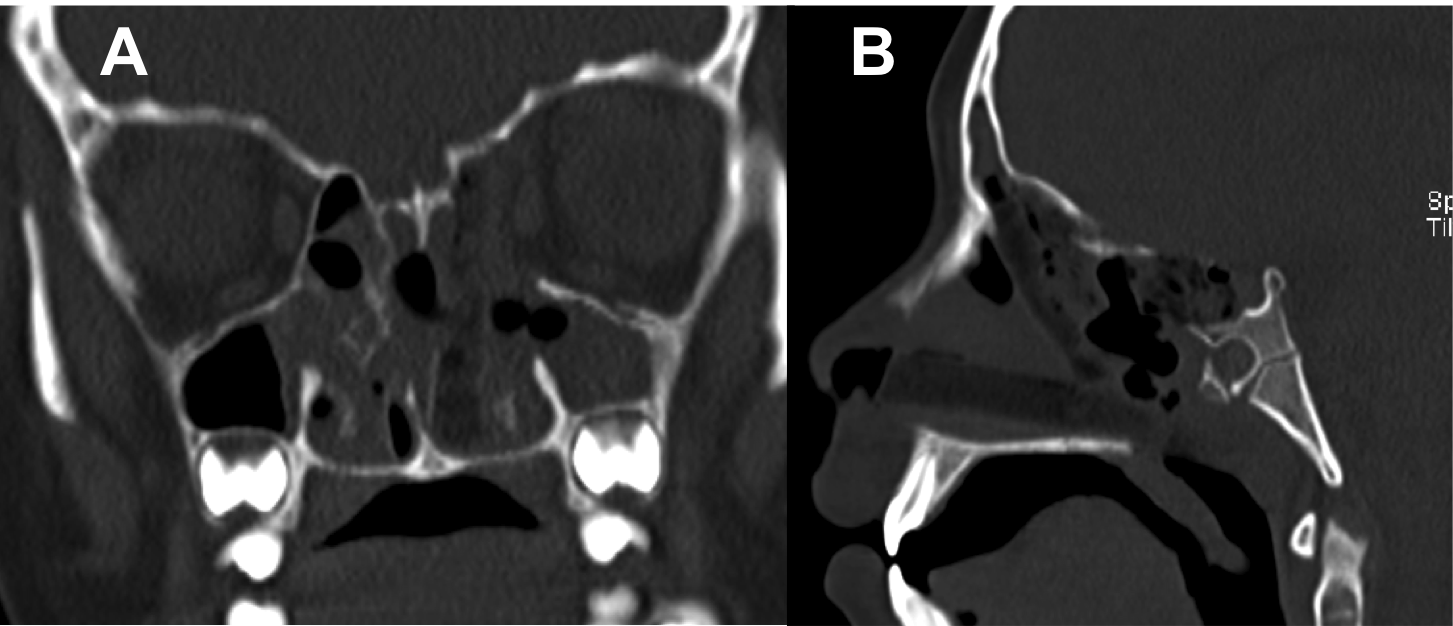

Introducción: La cirugía endoscópica endonasal se ha convertido en una herramienta fundamental para el manejo de patologías que comprometen la base de cráneo. En casos bien seleccionados, estas técnicas permiten resecciones quirúrgicas con una menor morbilidad sin comprometer los principios oncológicos de resección. Con el desarrollo de instrumental especializado, nuevas tecnologías y la experiencia de los cirujanos, la cirugía endoscópica endonasal se usa cada vez más en cirugía de base de cráneo en niños.

Diseño: Estudio observacional descriptivo de tipo serie de casos. Metodología: se describe la experiencia con pacientes pediátricos llevados a cirugía endoscópica endonasal para manejo de tumores de base de cráneo en el Instituto Nacional de Cancerología entre julio de 2014 y diciembre de 2016.

Resultados: Fueron intervenidos 8 pacientes entre los 2 y 14 años, con una edad promedio de nueve años y un seguimiento promedio de 16 meses. En el 75% se hizo una resección total del tumor. Un paciente requirió una reintervención y un paciente fue sometido a radiocirugía post-operatoria. 1 paciente falleció a pesar de múltiples intervenciones, quimioterapia y radioterapia.

Conclusión: La cirugía endoscópica endonasal para tumores de base de cráneo puede ser utilizada de forma segura en los pacientes pediátricos, es una técnica que en casos bien seleccionados pueden ofrecer excelentes resultados disminuyendo la morbilidad y complicaciones de las técnicas abiertas.